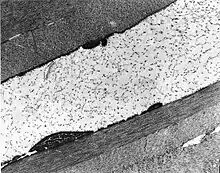

| The cornea is particularly opaque in the anterior stroma by slit-lamp biomicroscopy. | |

Congenital stromal corneal dystrophy (CSCD) is an extremely rare, autosomal dominant form of corneal dystrophy.[1] Only 4 families have been reported to have the disease by 2009.[2] The main features of the disease are numerous opaque flaky or feathery areas of clouding in the stroma that multiply with age and eventually preclude visibility of the endothelium. Strabismus or primary open angle glaucoma was noted in some of the patients. Thickness of the cornea stays the same, Descemet's membrane and endothelium are relatively unaffected, but the fibrils of collagen that constitute stromal lamellae are reduced in diameter and lamellae themselves are packed significantly more tightly.